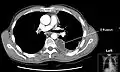

A large left-sided pleural effusion as seen on an upright chest X-ray

A pleural effusion is usually diagnosed on the basis of medical history and physical exam, and confirmed by a chest X-ray. Once accumulated fluid is more than 300 mL, there are usually detectable clinical signs, such as decreased movement of the chest on the affected side, dullness to percussion over the fluid, diminished breath sounds on the affected side, decreased vocal resonance and fremitus (though this is an inconsistent and unreliable sign), and pleural friction rub. Above the effusion, where the lung is compressed, there may be bronchial breathing sounds and egophony. A large effusion there may cause tracheal deviation away from the effusion. A systematic review (2009) published as part of the Rational Clinical Examination Series in the Journal of the American Medical Association showed that dullness to conventional percussion was most accurate for diagnosing pleural effusion (summary positive likelihood ratio, 8.7; 95% confidence interval, 2.2–33.8), while the absence of reduced tactile vocal fremitus made pleural effusion less likely (negative likelihood ratio, 0.21; 95% confidence interval, 0.12–0.37).[11]

Imaging

A pleural effusion appears as an area of whiteness on a standard posteroanterior chest X-ray.[12] Normally, the space between the visceral pleura and the parietal pleura cannot be seen. A pleural effusion infiltrates the space between these layers. Because the pleural effusion has a density similar to water, it can be seen on radiographs. Since the effusion has greater density than the rest of the lung, it gravitates towards the lower portions of the pleural cavity. The pleural effusion behaves according to basic fluid dynamics, conforming to the shape of pleural space, which is determined by the lung and chest wall. If the pleural space contains both air and fluid, then an air-fluid level that is horizontal will be present, instead of conforming to the lung space.[13] Chest radiographs in the lateral decubitus position (with the patient lying on the side of the pleural effusion) are more sensitive and can detect as little as 50 mL of fluid. Between 250 to 600mL of fluid must be present before upright chest X-rays can detect a pleural effusion (e.g., blunted costophrenic angles).[14]

Chest computed tomography is more accurate for diagnosis and may be obtained to better characterize the presence, size, and characteristics of a pleural effusion. Lung ultrasound, nearly as accurate as CT and more accurate than chest X-ray, is increasingly being used at the point of care to diagnose pleural effusions, with the advantage that it is a safe, dynamic, and repeatable imaging modality.[15] To increase diagnostic accuracy of detection of pleural effusion sonographically, markers such as boomerang and VIP signs can be utilized.[16]